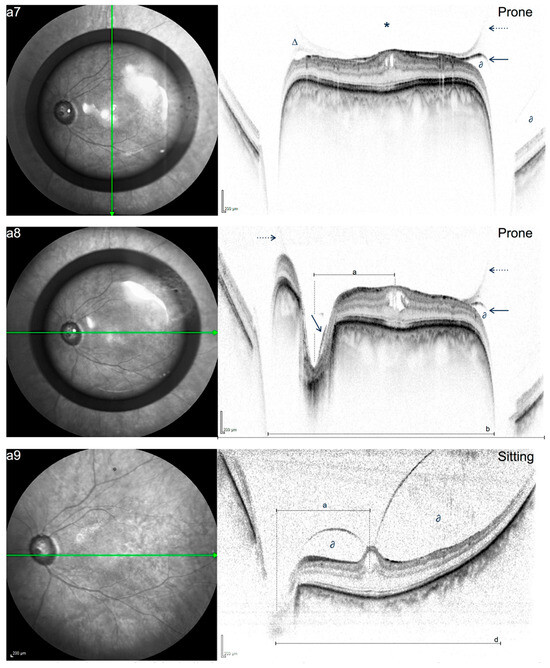

Mechanisms of Gas-Induced Posterior Vitreous Detachment: A Look Behind the Bubble Using Optical Coherence Tomography in Prone Position

Objectives: We aimed to visualize the interaction of intravitreal gas with the adjacent vitreomacular interface by using prone position (PP) SD-OCT and suggest possible mechanisms of action behind gas-induced posterior vitreous detachment (PVD) in pneumatic vitreolysis (PV). Methods: This was a descriptive–interpretative morphological [...] Read more.

Objectives: We aimed to visualize the interaction of intravitreal gas with the adjacent vitreomacular interface by using prone position (PP) SD-OCT and suggest possible mechanisms of action behind gas-induced posterior vitreous detachment (PVD) in pneumatic vitreolysis (PV). Methods: This was a descriptive–interpretative morphological study. Spectral domain OCT imaging in PP was carried out using a flexible scanning module (SD-OCT-Flex, Heidelberg Engineering) originally designed for bedside imaging. Routine imaging in sitting position was carried out using a regular SD-OCT-device (Heidelberg Engineering). Patients with symptomatic vitreomacular traction (VMT) scheduled for PV with perfluoropropane (C3F8, 0.3 mL) received both sitting and PP imaging immediately before and at regular follow-up visits during the first 3 post-procedural weeks, beginning 3 h after PV. Imaging was reviewed for positional changes of the gas bubble, posterior hyaloid membrane (PHM), VMT configuration, and retrohyaloidal fluid (RHF). Results: Three consecutive patients with VMT were included (age: 79, 80, 82 years). Before the procedure, no positional alterations were detected. After the intravitreal injection of gas, PP allowed for the precise discrimination of the PHM and the posterior border of the gas bubble. In contrast to regular SD-OCT in sitting position, PP imaging showed a flattened VMT by the gas bubble with consecutive displacement of RHF from the macular region to the midperiphery. Conclusions: This exploratory study describes PP imaging as a tool for the assessment of the morphologic dynamics between the posterior hyaloid membrane, retina, and gas bubble in pneumatic vitreolysis. PP in pneumatic vitreolysis causes the gas bubble to flatten the VMT and to push retrohyaloidal fluid to the midperiphery, possibly allowing for the release of persistent vitreoretinal adhesions and consequent PVD induction. Full article